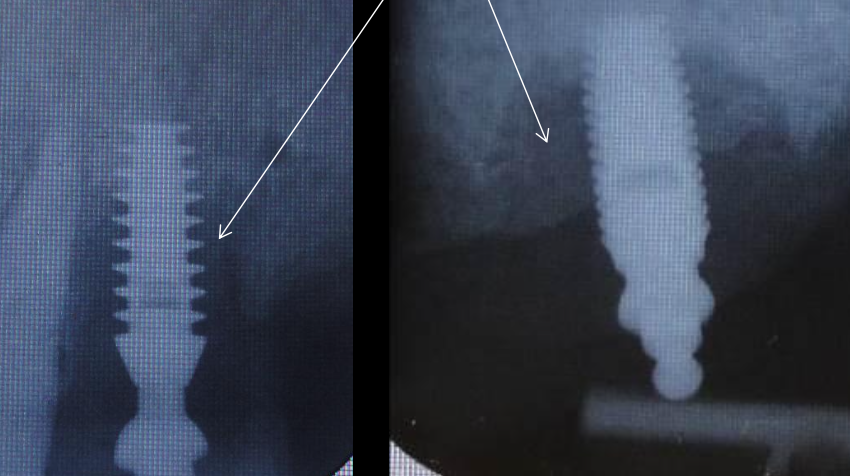

This is an example of failing implant-bone healing

Fibrous granulation tissue

What is the bone tissue response?

Fibrous tissue formation may occur ):

Non-vital bone may remain without revascularization ):

Bone healing will ensue :)